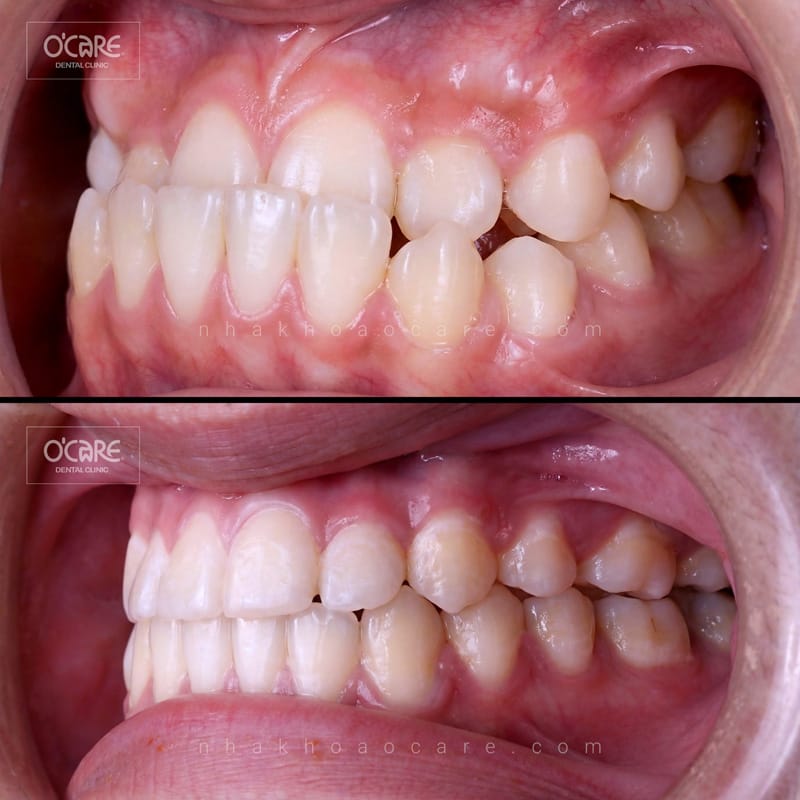

Tại Nha khoa Ocare, chúng tôi vừa hoàn tất thành công một ca niềng răng điều trị khớp cắn ngược cho trẻ em do BS.CKI Lương Thị Lài trực tiếp thực hiện. Kết quả mang lại sự thay đổi rõ rệt về diện mạo và chức năng ăn nhai, giúp bé tự tin hơn trên hành trình trưởng thành.

5. Kết quả sau điều trị khớp cắn ngược tại Nha khoa Ocare

Dưới bàn tay chuyên môn của BS.CKI Lương Thị Lài, các ca niềng răng cắn ngược tại Ocare đều đạt được những kết quả ấn tượng:

- Khớp cắn chuẩn: Hàm trên bao ngoài hàm dưới theo đúng tỷ lệ sinh lý.

- Răng đều đặn: Các răng được sắp xếp đúng vị trí, chuẩn đường giữa.

- Gương mặt hài hòa: Góc nghiêng cải thiện rõ rệt, cằm không còn bị nhô ra phía trước.

- Chức năng ăn nhai hoàn hảo: Bé ăn uống ngon miệng và phát âm chuẩn hơn.